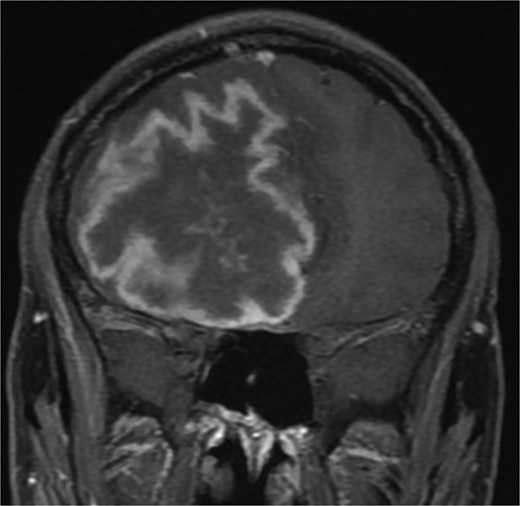

A previously healthy 36-year-old man presented to the emergency department complaining of persistent frontal headache, dizziness, and vomiting of 1 month duration, with no history of orbital complaints (e.g. visual deficits or swelling) or neurological deficits (e.g. limb weakness or seizure-like movements). On examination, the nasal endoscopy showed dry crusts filling the right nasal area. Therefore, due to the subtle symptoms’ origin, the patient was admitted, and a computed tomography (CT) scan of the head and a magnetic resonance imaging (MRI) of the brain were scheduled. The head CT scan revealed complete opacification of the maxillary, ethmoid, frontal, and sphenoid sinuses with bone destruction affecting the left lamina papyracea and roof of the ethmoid air cells (Fig. 1A). The brain MRI demonstrated similar findings with intra-orbital extension resulting in left global proptosis, which triggered concerns regarding fungal rhinosinusitis (Fig. 1B). Accordingly, the patient underwent functional endoscopic sinus surgery (FESS) with a right frontal craniotomy and partial removal of the infected brain tissue on the fourth day of his presentation. Specimens from both surgical sites were sent for pathology and cultures during the surgery. The histopathological results confirmed the diagnosis of CGIFRS, and A. flavus was found in the tissue culture. Postoperatively, the patient was stable, and intravenous antifungal treatment (amphotericin B and voriconazole) and high-dose steroid administration (dexamethasone) were started promptly following confirmation of CGIFRS via pathology. One week after the surgery, the patient’s condition suddenly deteriorated: he had a right fixed dilated pupil and spikes of fever. An urgent brain MRI with contrast was performed, which showed an intracranial abscess, and a significant midline shift to the right side (Fig. 2A and B). The patient, therefore, had a right decompression craniotomy and remained intubated and ventilated in the intensive care unit to receive the maximum medical therapy. However, despite this intensive treatment, the patient’s condition continued to worsen, and he ultimately died after 2 weeks.

(A and B) Brain MRI with contrast showing signs of intracranial abscess in the left side with mass effect and midline shift to the right side.